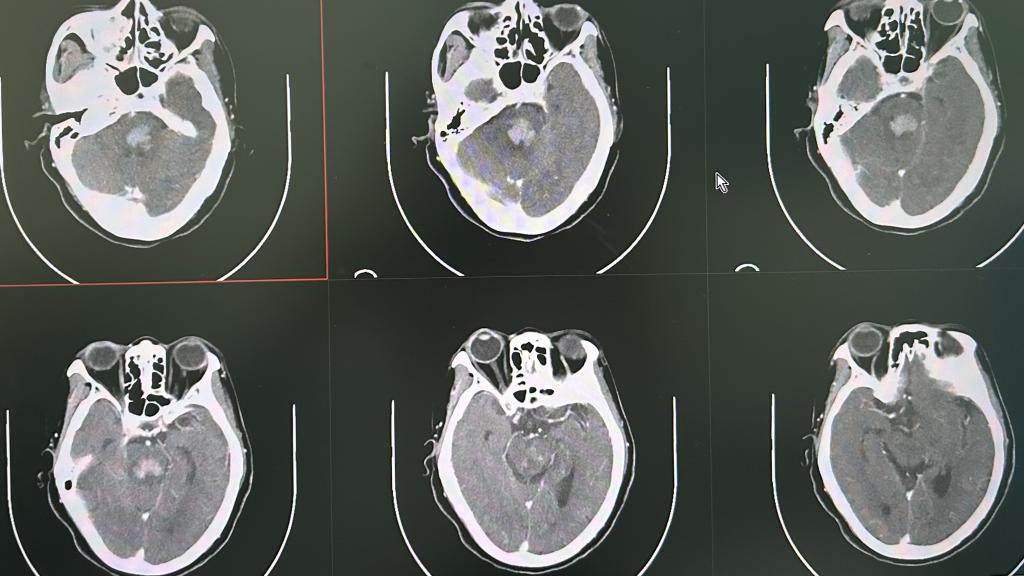

李松年,硕士研究生,主任医师,神经外科主任。广西医学会神经外科分会委员及神经介入组组员,广西医师协会神经外科分会委员、神经介入委员,广西抗癌协会神经肿瘤专业委员会委员,柳州市医学会神经外科分会副主任委员,柳州市脑损伤质控委员会副主任委员。先后到天津市环湖医院、广西医科大学第一附属医院、南方医科大学附属珠江医院进修,奥地利维也纳多瑙医院神经外科访问。 专长: 颅脑(脊髓)肿瘤、面肌痉挛、三叉...